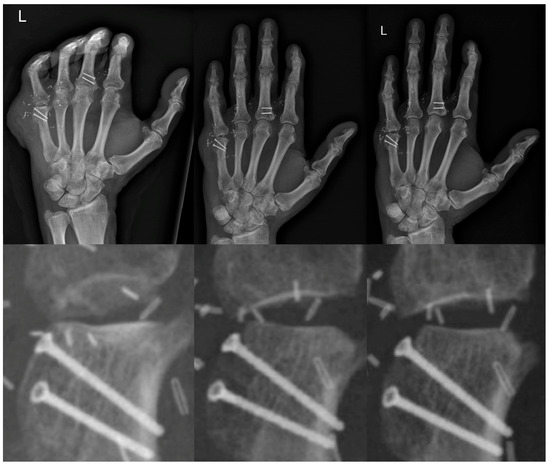

2. Case Report